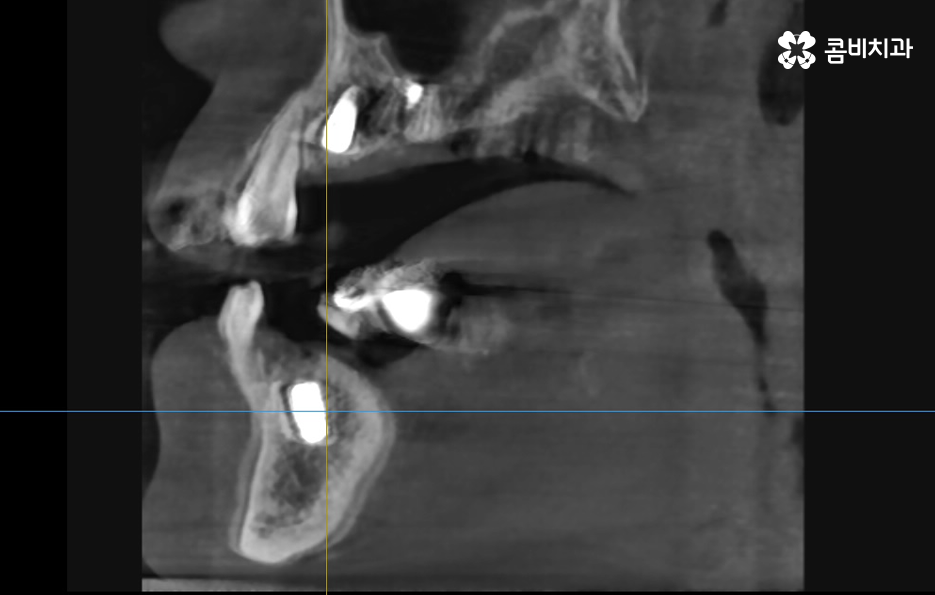

우선 임플란트 치료에 있어서 뼈이식이 필요한 이유에 대해 이해하시면 좋은데 임플란트의 치료 과정에서 뼈이식을 추가적으로 진행하는 이유에는 임플란트를 식립할 잇몸 뼈의 충분한 두께와 깊이가 확보되지 않을 때 임플란트를 안정적으로 식립하기 위해 뼈이식이 진행되고 있는데요

뼈이식은 뼈가루를 말랑하게 점토처럼 반죽하여 잇몸 안에 이식을 하고 단단하게 기존의 뼈처럼 굳기 까지 평균적으로 약 2~4개월 정도가 걸리는데 환자분의 건강 상태에 따라서는 6개월 이상도 걸릴 수 있어요

뼈이식의 양은 환자분들에 따라서 차이가 있기 때문에 뼈이식을 하는 정도 차이와 현재 환자분의 전신건강, 잇몸 상태 등에 따라서 보통 차이가 난다고 보시면 좋을 거예요